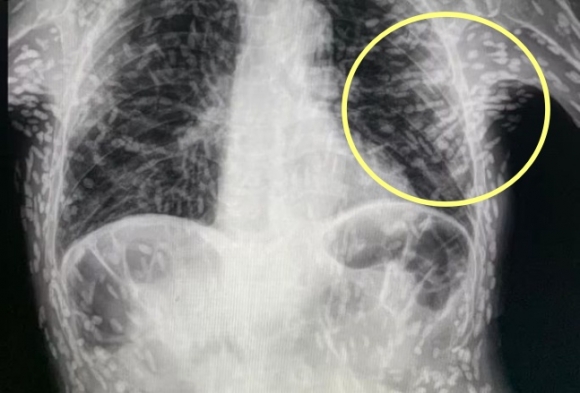

기침으로 인한 고통을 호소한 환자를 진료하던 의료진은 환자의 엑스레이 사진을 보고 경악했습니다. 엑스레이 촬영물에는 여러 마리의 촌충과 유충이 가득 찍혀있는 것이었습니다.

브라질의 한 의료진이 소셜네트워크서비스(SNS)에 기생충에 감염된 엑스레이 사진을 공개했습니다. 사진에는 몸속에 있는 기생충이 죽어 석회화된 수백 개의 점 형상이 보였습니다.

특히 유충이 근육이나 뇌 조직에 침투한 모습은 매우 충격적이었습니다. 이러한 증상은 유구조충의 유충에 의한 인체감염증으로, 유구 낭미충증이라고도 불립니다.

유구낭미충증은 주로 인간의 장에 사는 촌충의 유충이 근육이나 뇌로 침투할 때 발생합니다. 이 유충은 근육과 뇌에서 낭종과 같은 결절을 형성하기도 합니다.